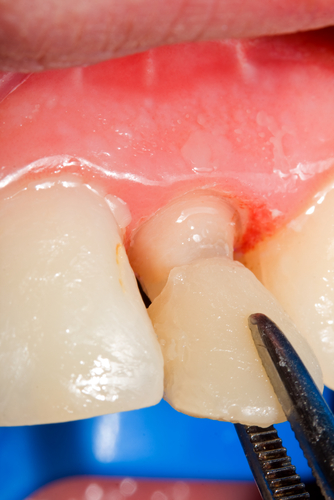

What is a Periodontal Pocket? Is It Bad? Not Exactly...

A pocket is our dental name for the space that naturally exists between the gum and the tooth. Another name for a pocket is a sulcus. This is part of our normal anatomy. The gum does not attach to the tooth where our eyes tell us it does. Instead, it folds in and attaches lower on the tooth at a...  Read More